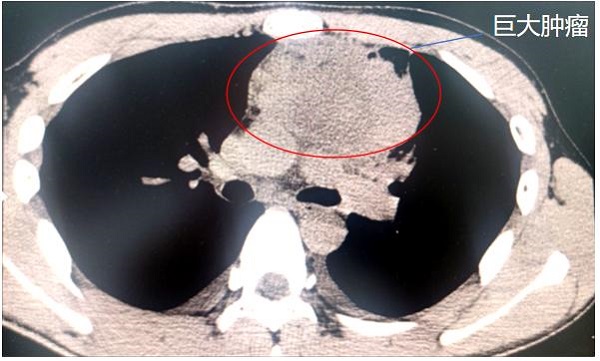

最終,在家人的陪伴下,林杰來到重醫(yī)附屬大學(xué)城醫(yī)院就診。CT檢查結(jié)果顯示,林杰的上縱隔頸胸交界處盤踞著直徑達(dá)10厘米的腫瘤,如同成年男性拳頭大小,并且緊貼心臟、主動(dòng)脈弓分支及無名靜脈。

前上縱隔頸胸交界處巨大腫瘤。重醫(yī)附屬大學(xué)城醫(yī)院供圖